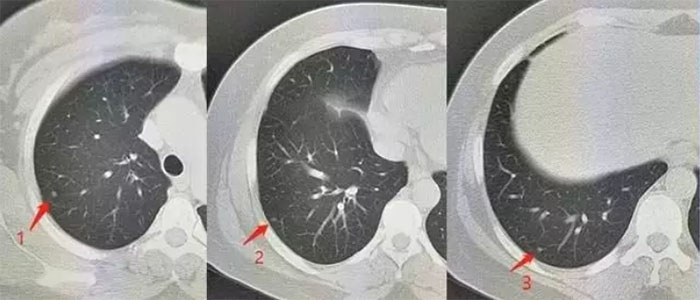

肺结节为小的局灶性、类圆形、影像学表现密度增高的阴影,可单发或多发,不伴肺不张、肺门肿大和胸腔积液。孤立性肺结节无典型症状,常为单个、边界清楚、密度增高、直径≤3 cm且周围被含气肺组织包绕的软组织影。

肺部小结节并不等于早期肺癌,肺内很多疾病都会形成结节,良性的如炎症、结核、霉菌、亚段肺不张、出血、等。因此肺内的小结节性病灶,可能的诊断可以说是多种多样,良性的包括炎性假瘤、错构瘤、结核球、真菌感染、硬化性肺细胞瘤等。恶性的则可能是原发性肺癌或肺内转移癌。当然部分良性病变,长时间之后也可能转化为恶性。据人群大样本的统计表明,直径大于25px的肺内单发小结节,恶性的占到一半以上。

这样的数据告诉我们,决不可轻视体检时无意发现的肺内小结节。CT检查发现的肺部小结节,必须要高度重视,因为其中有一定比例是早期肺癌,所以必要的早期检测筛查,是必不可少。